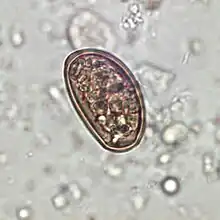

Traditionally, diagnosis for dicrocoeliasis infection involves the identification of Dicrocoelium dendriticum eggs in the faeces of a human or other animal. However, in humans, eggs in the stool may be a result of ingesting raw infected animal liver and may not in fact indicate dicrocoeliasis.[16] Therefore, examining bile or duodenal fluid for eggs is a more accurate diagnostic technique in combination with a liver-free diet.[14]